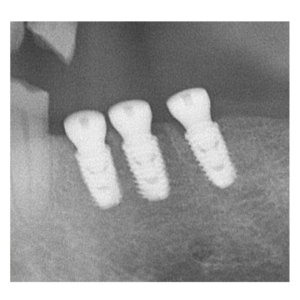

治療途中のインプラント症例

治療途中のインプラント症例です。

しっかり噛めるようにしたい |

60歳 男性 |

1時間 |

治療費(インプラント手術費) |

¥1,050,000(税別) |

| リスクと注意点 |

腫れ・痛み・神経損傷・インプラント周囲炎・骨吸収 など |